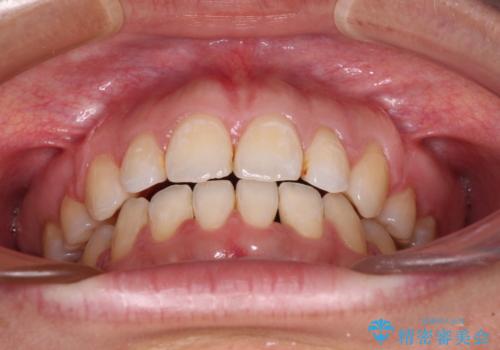

- 唇の閉じにくさを気にして来院された患者様です。

上下左右第一小臼歯4本を抜歯し、ワイヤー装置にて口元を引っ込めるよう矯正治療を行うこととしました。